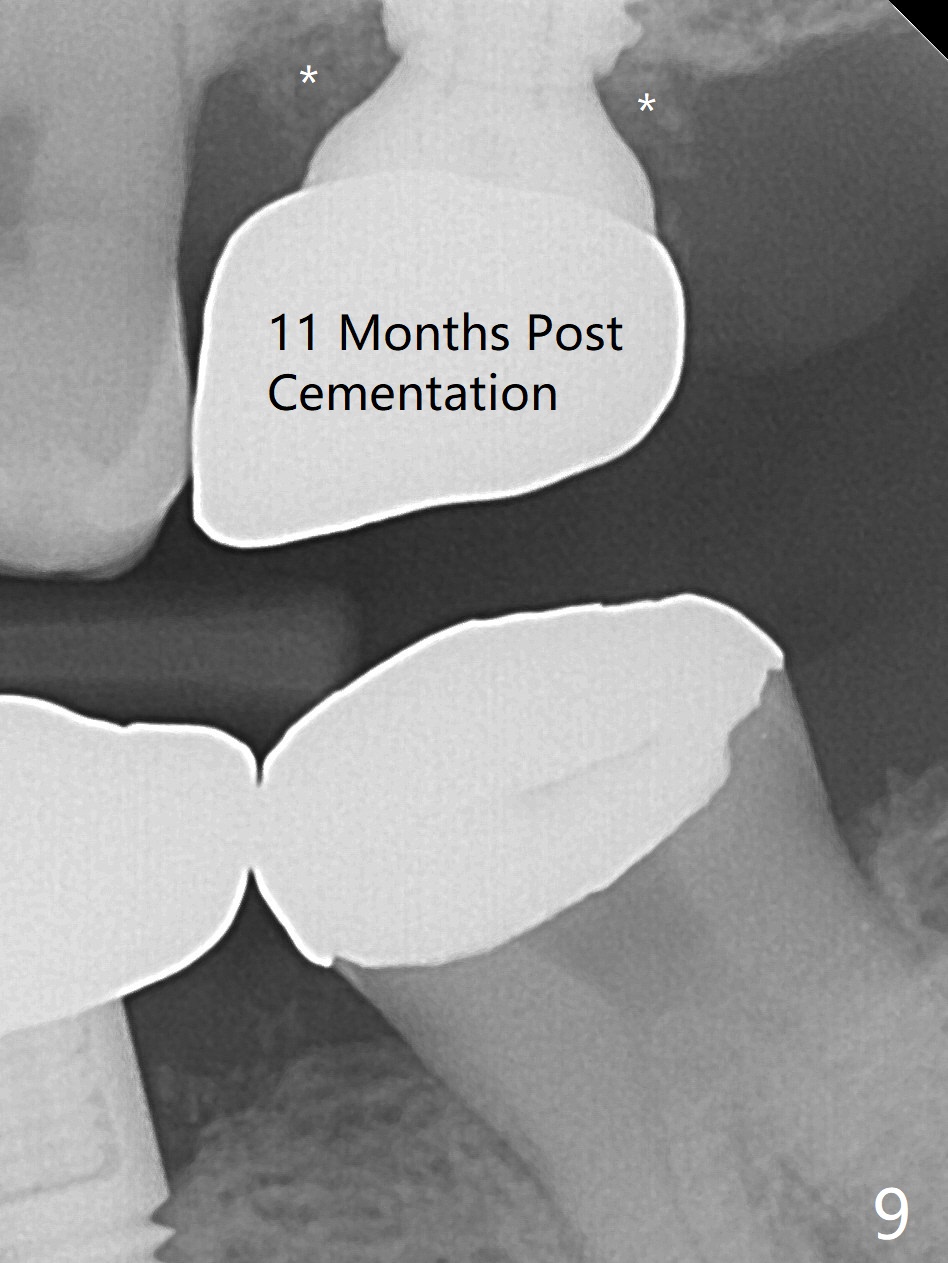

Extraction of the tooth #15 with short clinical crown (suggesting bruxism, Fig.1) reveals a vertical root fracture (Fig.2 <). It seems unnecessary and difficult to create osteotomy in the mesial slope. What can be done is to place starter and 2 mm drills as mesial as possible (Fig.3 (red dashed line: sinus floor). After use of Lindamann bur to move the osteotomy mesially and sequential osteotomy until 3.8x18 mm, a 4.5 mm tap is inserted with clearance from the impacted tooth #16 (Fig.4). A 5x15 mm implant is placed with >60 Ncm with clearance from the 3rd molar (Fig.5,6). If the impacted tooth were removed, the primary stability is expected to be reduced. Impression is taken 6 months postop with 19/20 implants (Fig.7). The bone graft remains in the crestal area immediately and 11 months post cementation (Fig.8,9 *). In the other word, new crestal bone forms after extraction.